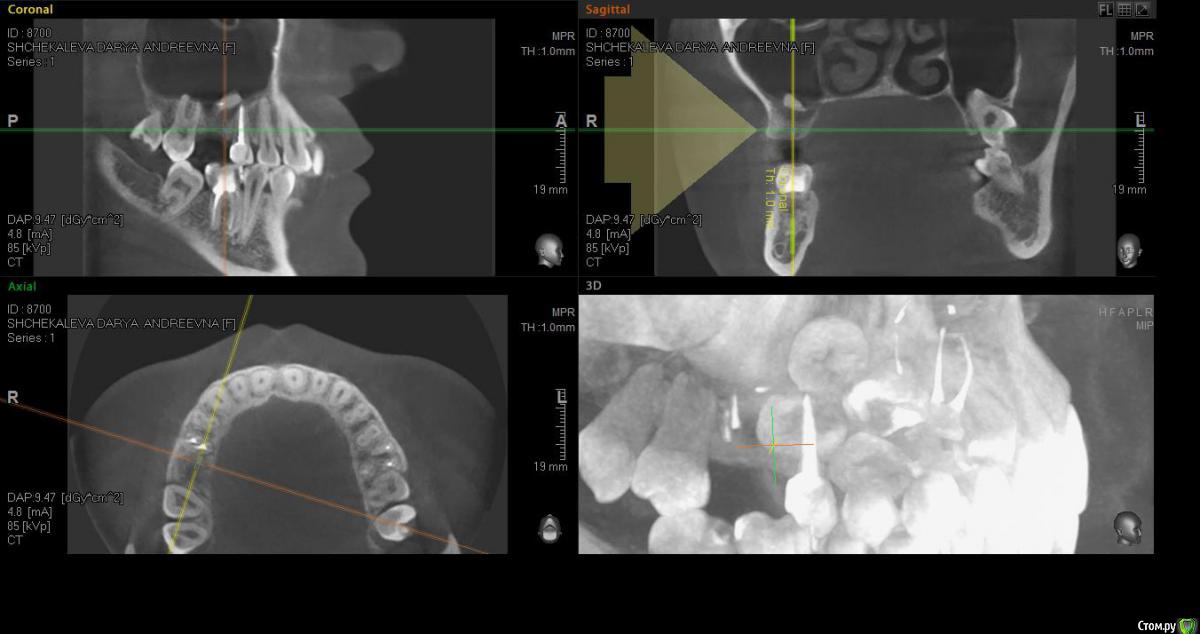

alekszander Опубликовано 14 марта, 2016 Поделиться Опубликовано 14 марта, 2016 Собственно вопрос кто сам доставал какие особенности? Или все же лучше к ЛОРу через эндоскоп?Боюсь только что корень с мембраной создал спайку и во время удаления просто порву мембрану.Дальние корни попробую аккуратно периотомом убрать. Ссылка на комментарий

faity Опубликовано 14 марта, 2016 Поделиться Опубликовано 14 марта, 2016 Можно со стороны альеолярки влезть, можно сразу окно выпилить.Для начала делаете доступ для визуализации, визуализируете апекс, потом аккуратно цепляете апикально чтобы мембрану не порвать, подойдёт кюретажка Лукаса маленькая 2мм и как с кистой или грануляцией вылущиваете. Если протолкнули- снимок и окно в проекции. 1 Ссылка на комментарий

Глеб Митрофанов Опубликовано 15 марта, 2016 Поделиться Опубликовано 15 марта, 2016 3 Ссылка на комментарий